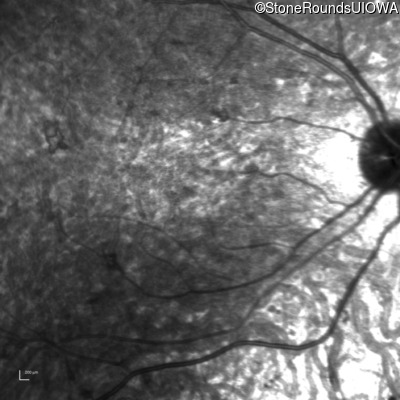

Infrared Fundus Photograph - Right - 10/600 sc

Exemplar